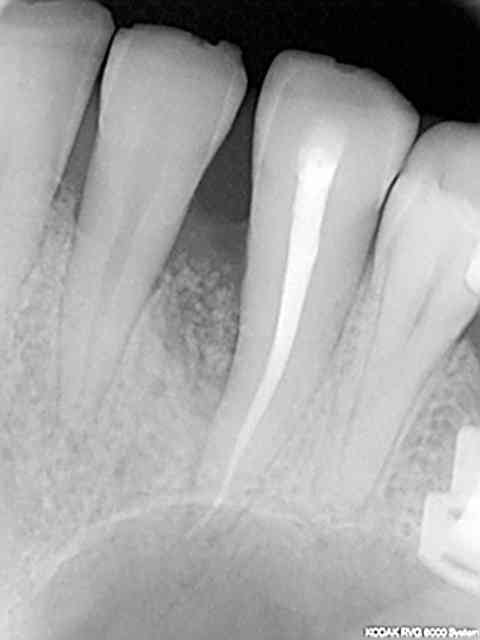

rvg avant endo et 3 mois après endo retouche occlusale et rtr +prf on voit le "fut.." en 15 !

c'est le coté droit qui a été équipé en dernier c'est de ce coté que commence les problèmes cad fenestration en haut fracture dentaire en bas.